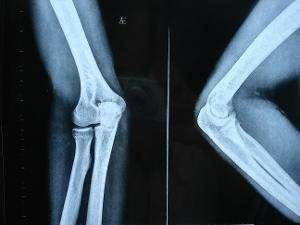

橈骨頭半脫位

4、X線檢查陰性。參考資料